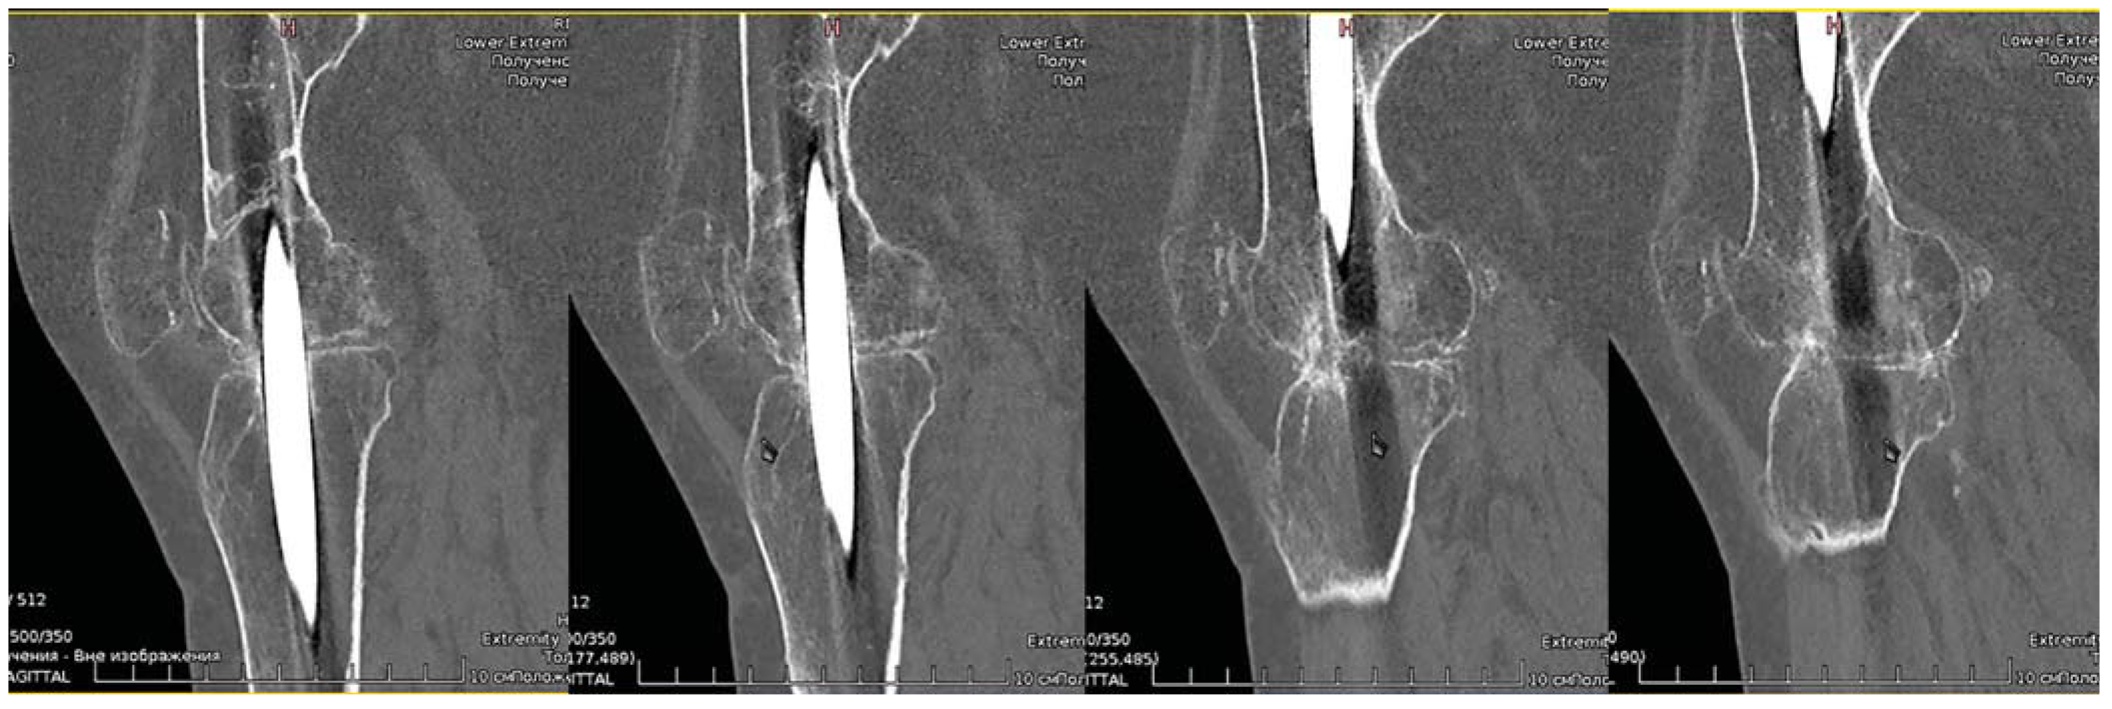

На рентгенограмме правой нижней конечности (через 3 мес после операции) определялась консолидации в зоне остеотомии бедренной кости, через 6 мес произошло формирование костного анкилоза коленного сустава, что было подтверждено данными компьютерной томографии (рис. 9).

Для оценки результатов лечения пациентки были использованы этапная рентгенография прооперированной конечности, компьютерная томография и шкала KOOS, позволяющая выявить функцию коленного сустава и степень качества жизни пациента [15]. До операции у обследуемой пациентки был выявлен крайне низкий функциональный уровень, составивший по шкале KOOS 14,3 балла, через 12 мес после операции показатель достиг 67,3 балла [15].

Рис. 9. Компьютерные томограммы коленного сустава пациентки через 6 мес после операции.

Fig. 9. CT scans of the knee joint of the patient in 6 months after the surgery.